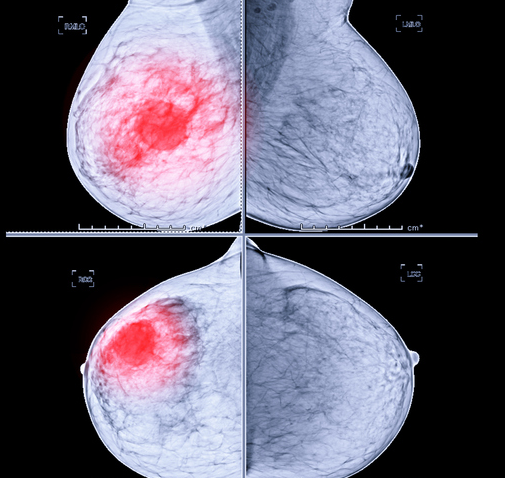

유방암은 유방에 암세포가 생겨서 주변으로 퍼져나가는 악성 종양입니다. 대부분의 유방암은 유관 세포에서 시작하는데요. 이 유관 세포 소엽의 상피 세포에서 발생하는 암을 의미합니다.

유방암 종류는 몇 가지가 있는데, 가장 많은 비율을 차지하는 것이 바로 침윤성 유관암으로 전체의 80% 이상을 차지하고 유관의 기저막을 침범합니다. 다음으로 높은 비율은 침윤성 소엽암으로 전체의 10% 정도를 차지합니다. 이 밖에 유관 상피내암, 소엽 상피내암, 유방 파제트병 등이 있습니다.